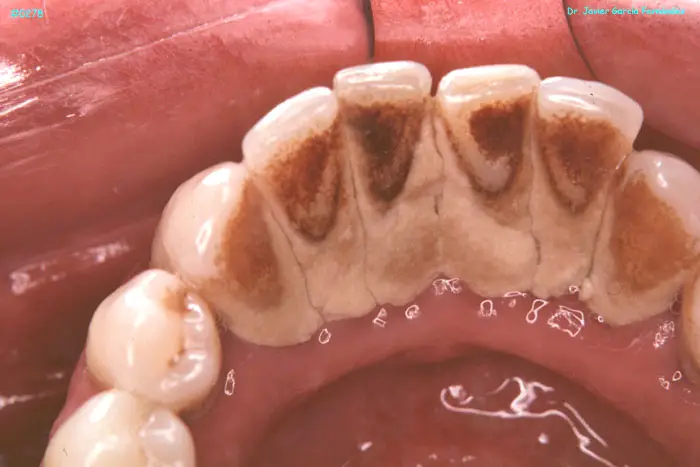

ATLAS DE CIRUGIA PERIODONTAL

image325